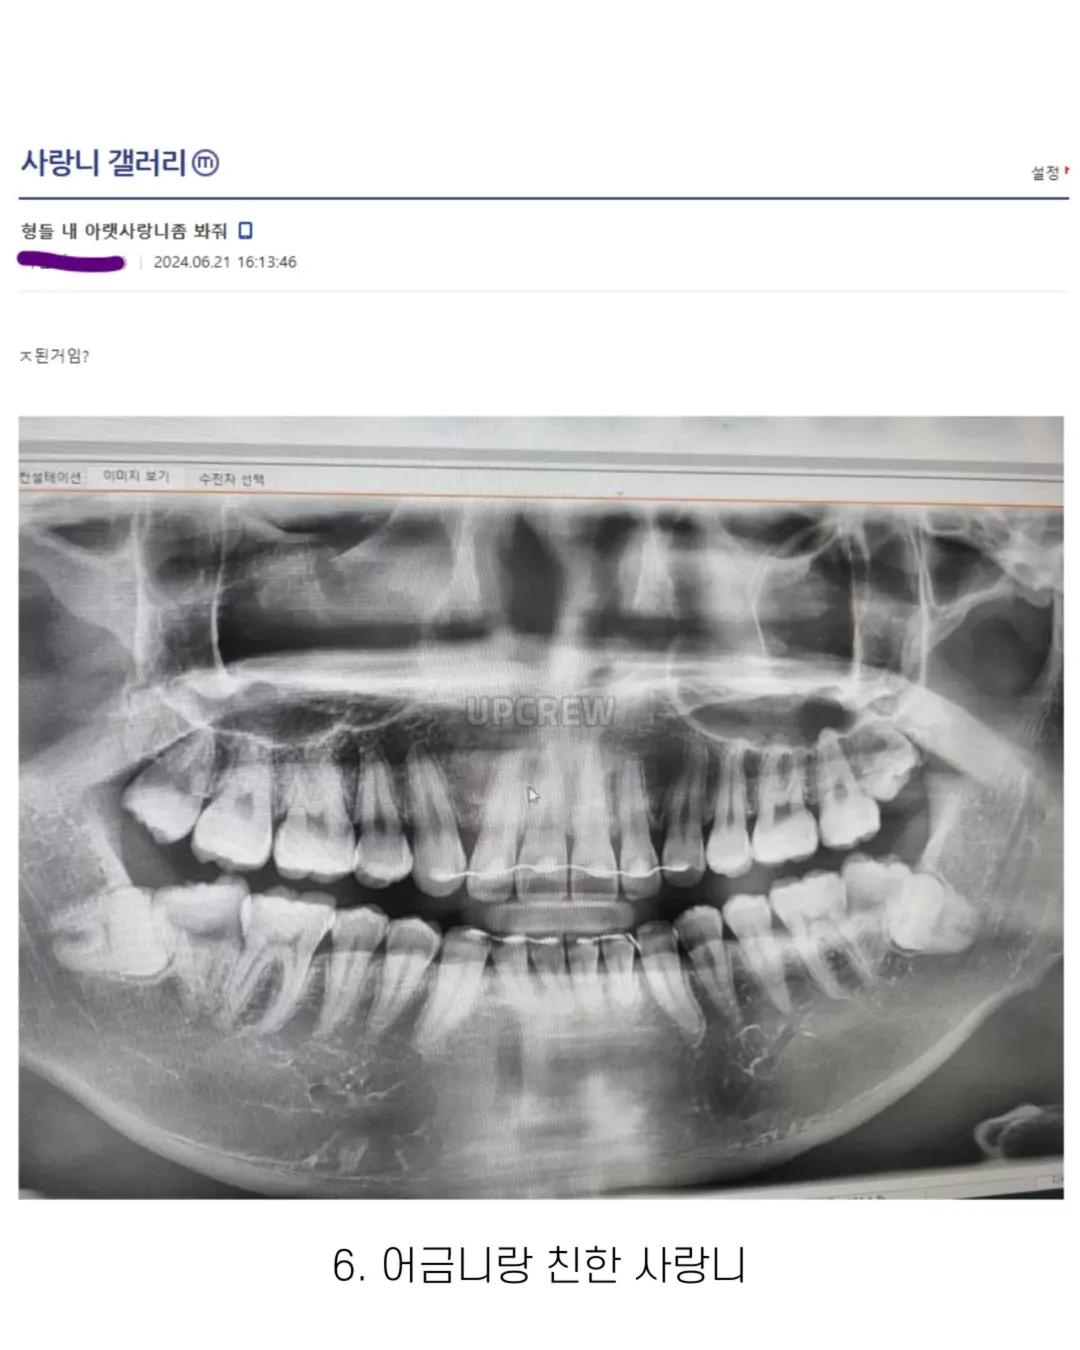

사랑니 갤러리의 특이한 사랑니들 (약혐 주의)

3개 누워있는거랑 14번은 진짜 어카냐..

과잉치도 있긴 한데 대부분 발육과정 문제로 제 2대구치랑 사랑니가 겹친 양상임.... 케이스 모두....최악이다 진짴ㅋㅋㅋㅋㅋㅌㅌㅌㅌㅌㅌㅌ